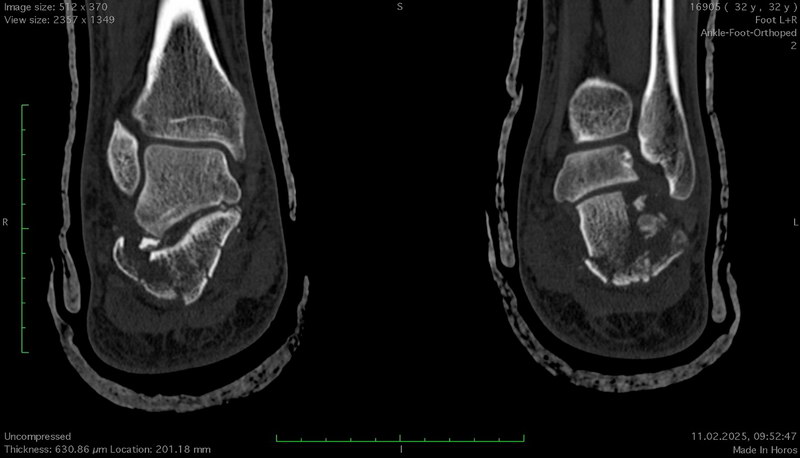

Але рентген — лише силует, тінь реальності. Справжню карту руйнувань малює комп’ютерна томографія (КТ) — безжальний картограф, що шар за шаром зрізає тканини, показуючи перелом у всій його тривимірній жорстокості. Тут видно кожен уламок, кожну тріщину, кожне зміщення. КТ дозволяє побачити те, що приховане від звичайного погляду — як суглобова поверхня розламана на шматки, наче дзеркало, що впало на підлогу.

Саме ці знімки визначають, чи зможе лікар зібрати цю «складанку» назад, чи доведеться жити з компромісом.